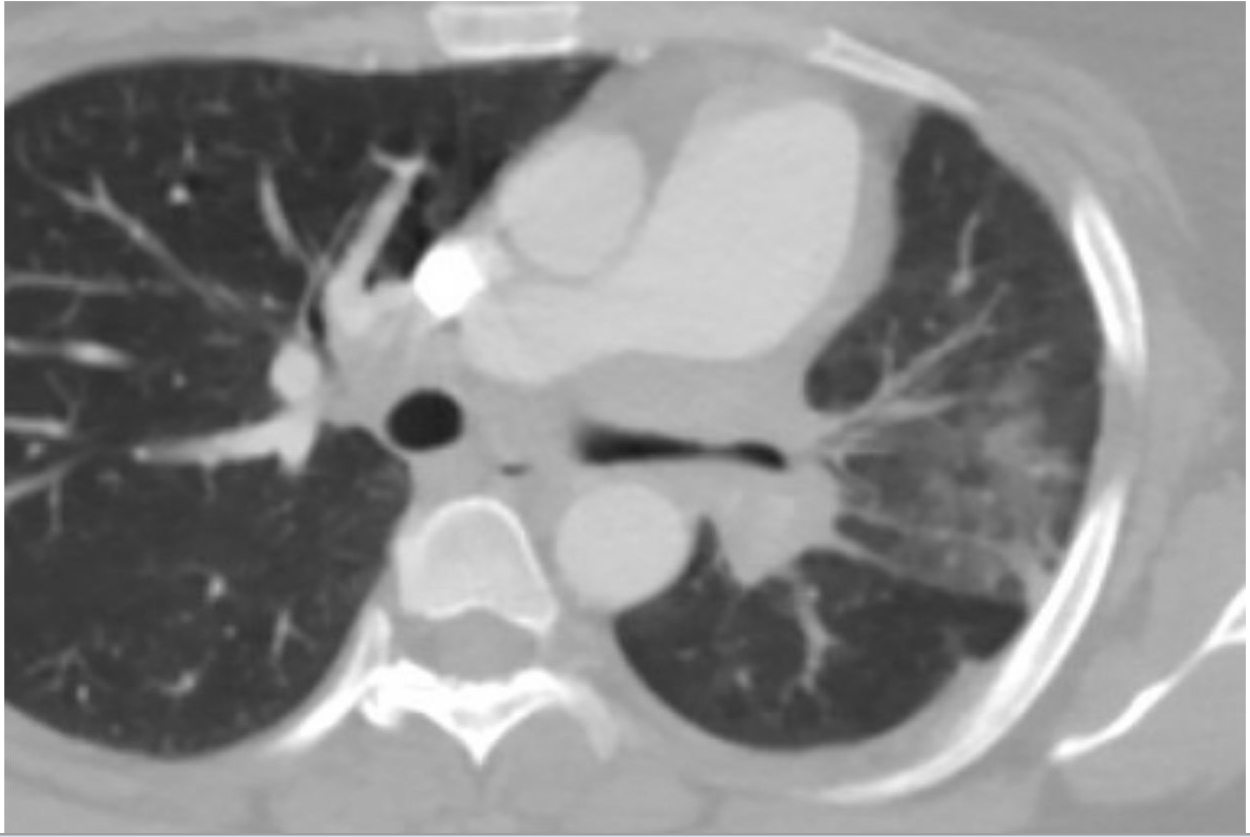

Fibrosing Mediastinitis (FM) is a rare, progressive disorder characterized by fibrous tissue growth in the mediastinum, the compartment containing the heart, major blood vessels, trachea, and esophagus. This abnormal process can compress these structures, leading to serious complications. It is most commonly associated with Histoplasmosis but can be caused by other infections, autoimmune diseases, radiation therapy, or idiopathically. FM typically affects women in their third or fourth decades, but pregnancy-associated cases are extremely rare. Existing case reports show variable outcomes based on the extent of vascular and airway compromise and the timing of diagnosis. We present a case of FM in a pregnant patient, complicated by antepartum hemoptysis and left lung atelectasis, who was managed with an interdisciplinary approach including pulmonology and cardio-obstetrics.

A 37-year-old G1P1 female with known idiopathic FM and a previous mediastinectomy presented at 23 weeks and 3 days with preterm labor and cervical dilation to 4 cm. She received steroids and magnesium for fetal neuroprotection. In the days prior to delivery, she experienced hemoptysis, prompting pulmonology consultation. She was managed conservatively with chest physiotherapy and nebulizers. The patient had no more hemoptysis and at 24 weeks and 1 day, she underwent classical cesarean delivery for breech presentation and non-reassuring fetal heart tones. The neonate was admitted to NICU and the patient was discharged in stable condition. Outpatient imaging revealed a stable calcified mediastinal mass causing 80% narrowing of the left main bronchus and left lung atelectasis. Subsequent bronchoscopy with balloon dilation improved airway patency, but stenting was deferred.

FM can remain stable during pregnancy, but physiologic changes in pregnancy such as increases in blood volume and cardiac output can be exacerbated by FM, potentially leading to pulmonary hypertension and reduced blood flow to the uterus. Notably, FM-related airway obstruction may not always present with overt respiratory distress and can be managed conservatively in select patients. Also, while balloon dilation may offer symptomatic relief, stenting decisions must be individualized based on functional status and patient preference. Finally, early multidisciplinary collaboration is crucial to prepare for peripartum respiratory complications in patients with known mediastinal pathology.